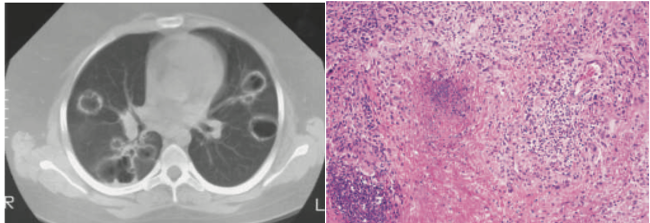

• 정의: 상/하기도 육아종, 전신 소혈관 혈관염, Pauci-immune 사구체신염을 특징으로 하는 3대 증상(triad)

• : 다발성, 양측성 공동성 결절(cavitary nodules), 객혈

• 확진: 조직생검에서 괴사성 육아종성 혈관염 확인 (폐생검이 가장 진단율 높음)